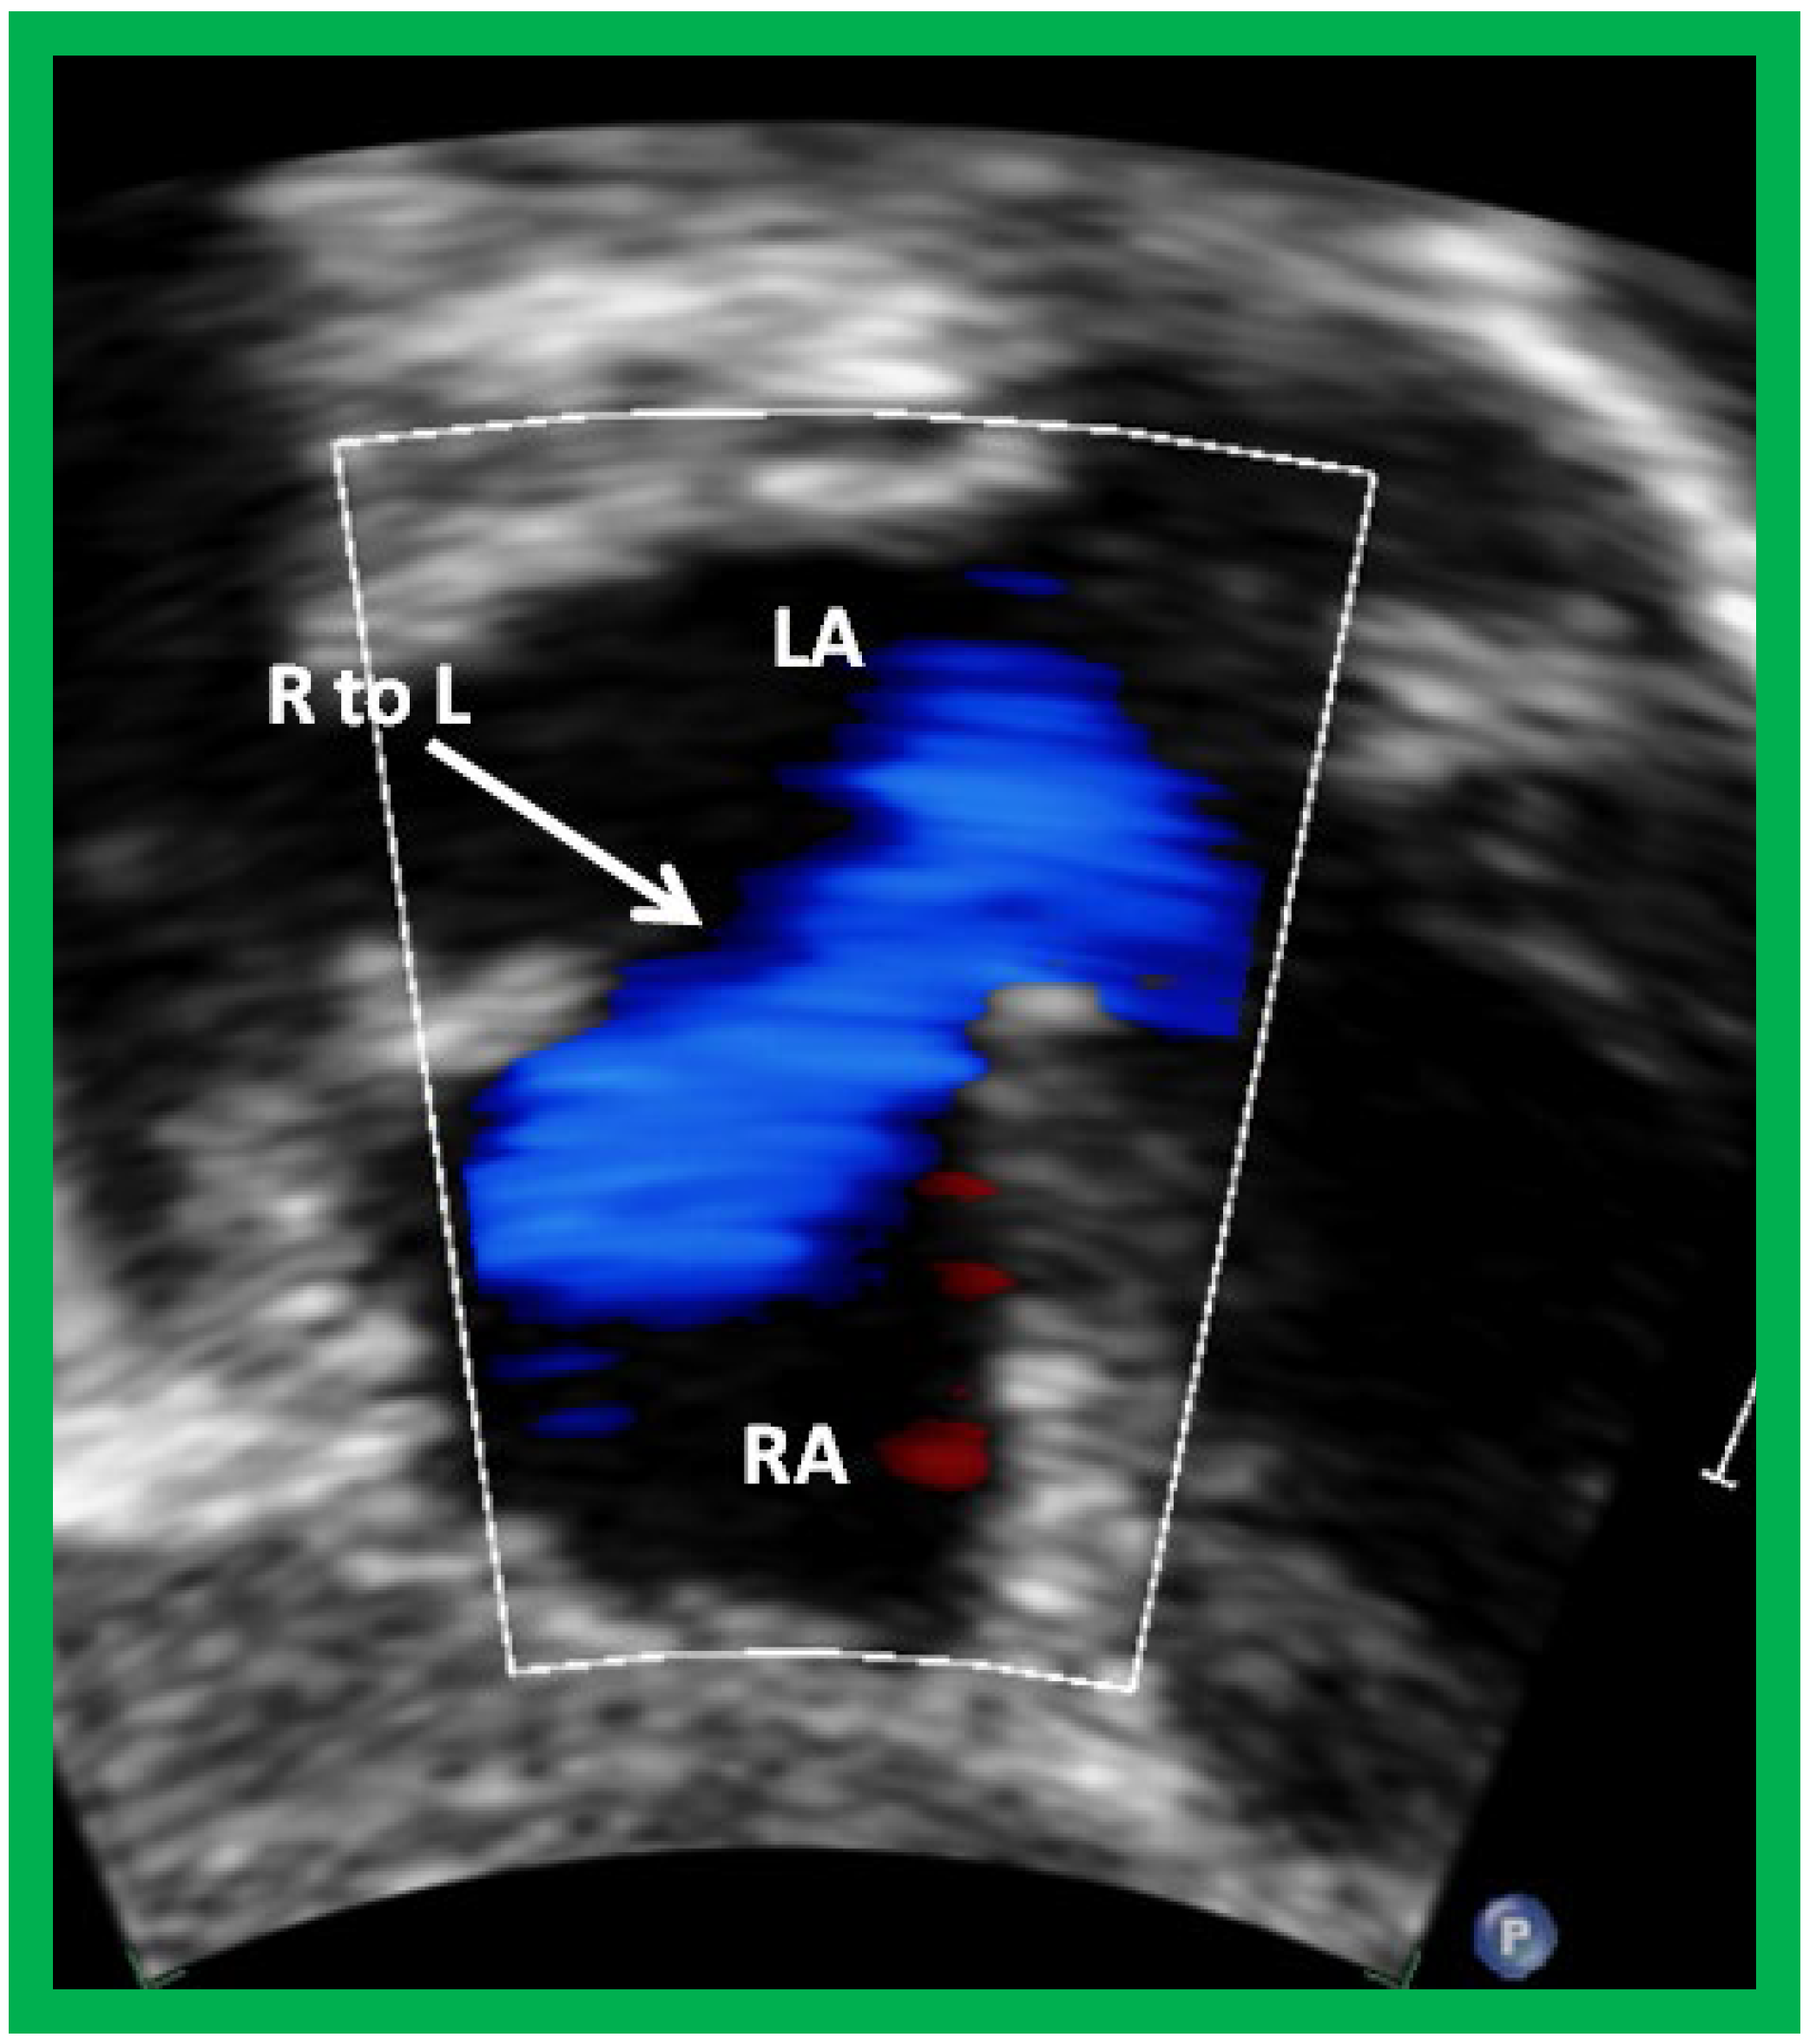

Figure 9. Selected video frame from subcostal view of a patient with tricuspid atresia demonstrating right to left (R to L) shunt (arrow) across the interatrial communication. LA, left atrium; RA, right atrium. Reproduced from Reference [29].

Following the demonstration of the atretic tricuspid valve, the sizes of the cardiac chambers are evaluated both by M-mode (Z scores) and 2D echocardiography; an enlarged RA, LA and LV and a small RV are seen (Figure 4, Figure 5 and Figure 6). Pulsed (not shown) and color Doppler (Figure 9) studies are helpful in illustrating right to left shunt across a PFO or an ASD.